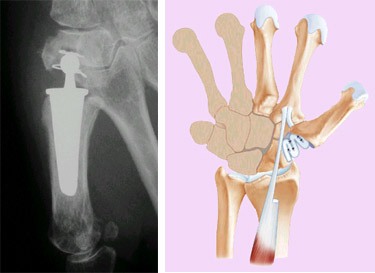

Les traitements chirurgicaux classiques de la rhizarthrose sont la trapézectomie et la pose d'une prothèse trapézométacarpienne.

La prothèse trapézométacarpienne consiste à placer une prothèse pour rétablir la longueur de la colonne du pouce.